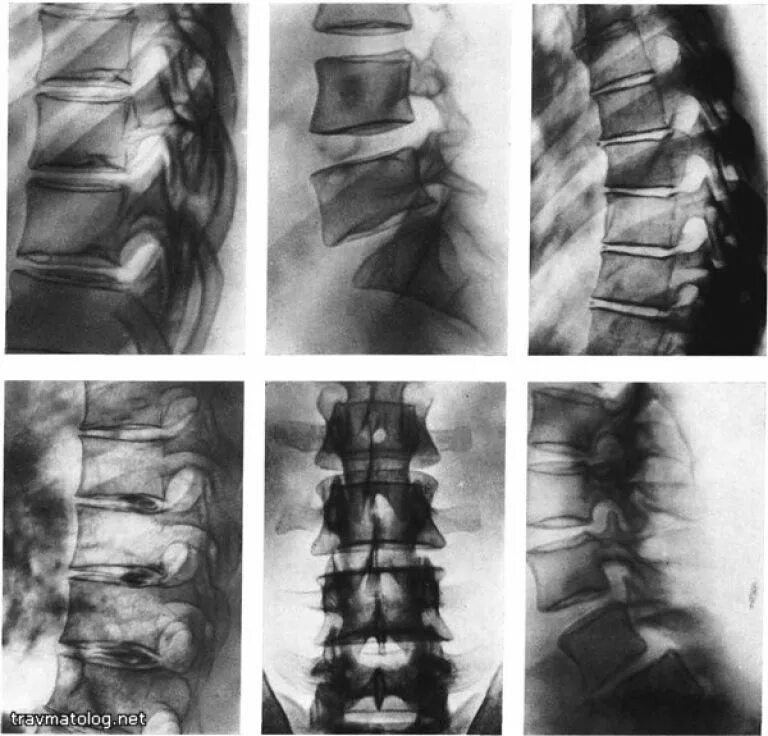

Дегенеративные изменения крестцового отдела